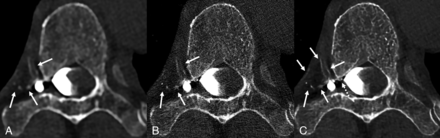

Axial low-energy thresholded (T3D) images in a 50-year-old woman with a right T6 CVF. Images were reconstructed using a Br56 kernel (A), a sharper Qr89 kernel (B), and a Qr89 kernel after denoising with the trained model (C), all presented at the same section and window/level settings. The Br56 kernel demonstrates amorphous opacification around a right T6 diverticulum (A, solid arrow) and possible venous opacification in the internal vertebral venous plexus (A, dashed arrows). The Qr89 kernel more clearly delineates individual external vertebral veins (B, solid arrow), though the image is overall degraded secondary to noise (B, dashed arrows). The denoised Qr89 image clearly identifies all the involved veins, including the external vertebral veins (C, solid arrow) and ventral/dorsal internal vertebral venous plexus (C, dashed arrows).